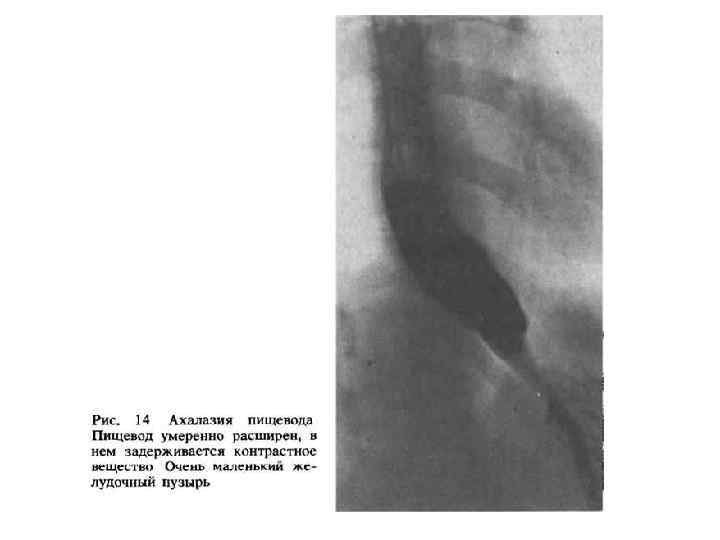

Классификация ахалазии • I тип характеризуется умеренным сужением дистального отрезка пищевода и незначительным супрастенотическим расширением пищевода (до 6 см). Сохраняется его цилиндрическая или овальная форма. • При ахалазии II типа отмечается выраженное сужение дистальной части пищевода и его значительное супрастенотическое расширение (иногда до 16 18 см), из за чего пищевод часто принимает N образную форму. В зависимости от вида дискинезии грудного отдела пищевода выделяют гипермоторную и гипомоторную формы ахалазии кардии, а в зависимости от тяжести клинического течения заболевания стадии компенсации и декомпенсации.

Стадии (рентгенологически) I – коническое сужение, барий быстро попадает в желудок II – расширение в грудной части пищевода, в которой скапливается жидкость III – резкое расширение пищевода. Опорожнение пищевода задерживается на несколько суток

Ахалазия пищевода II III стадии